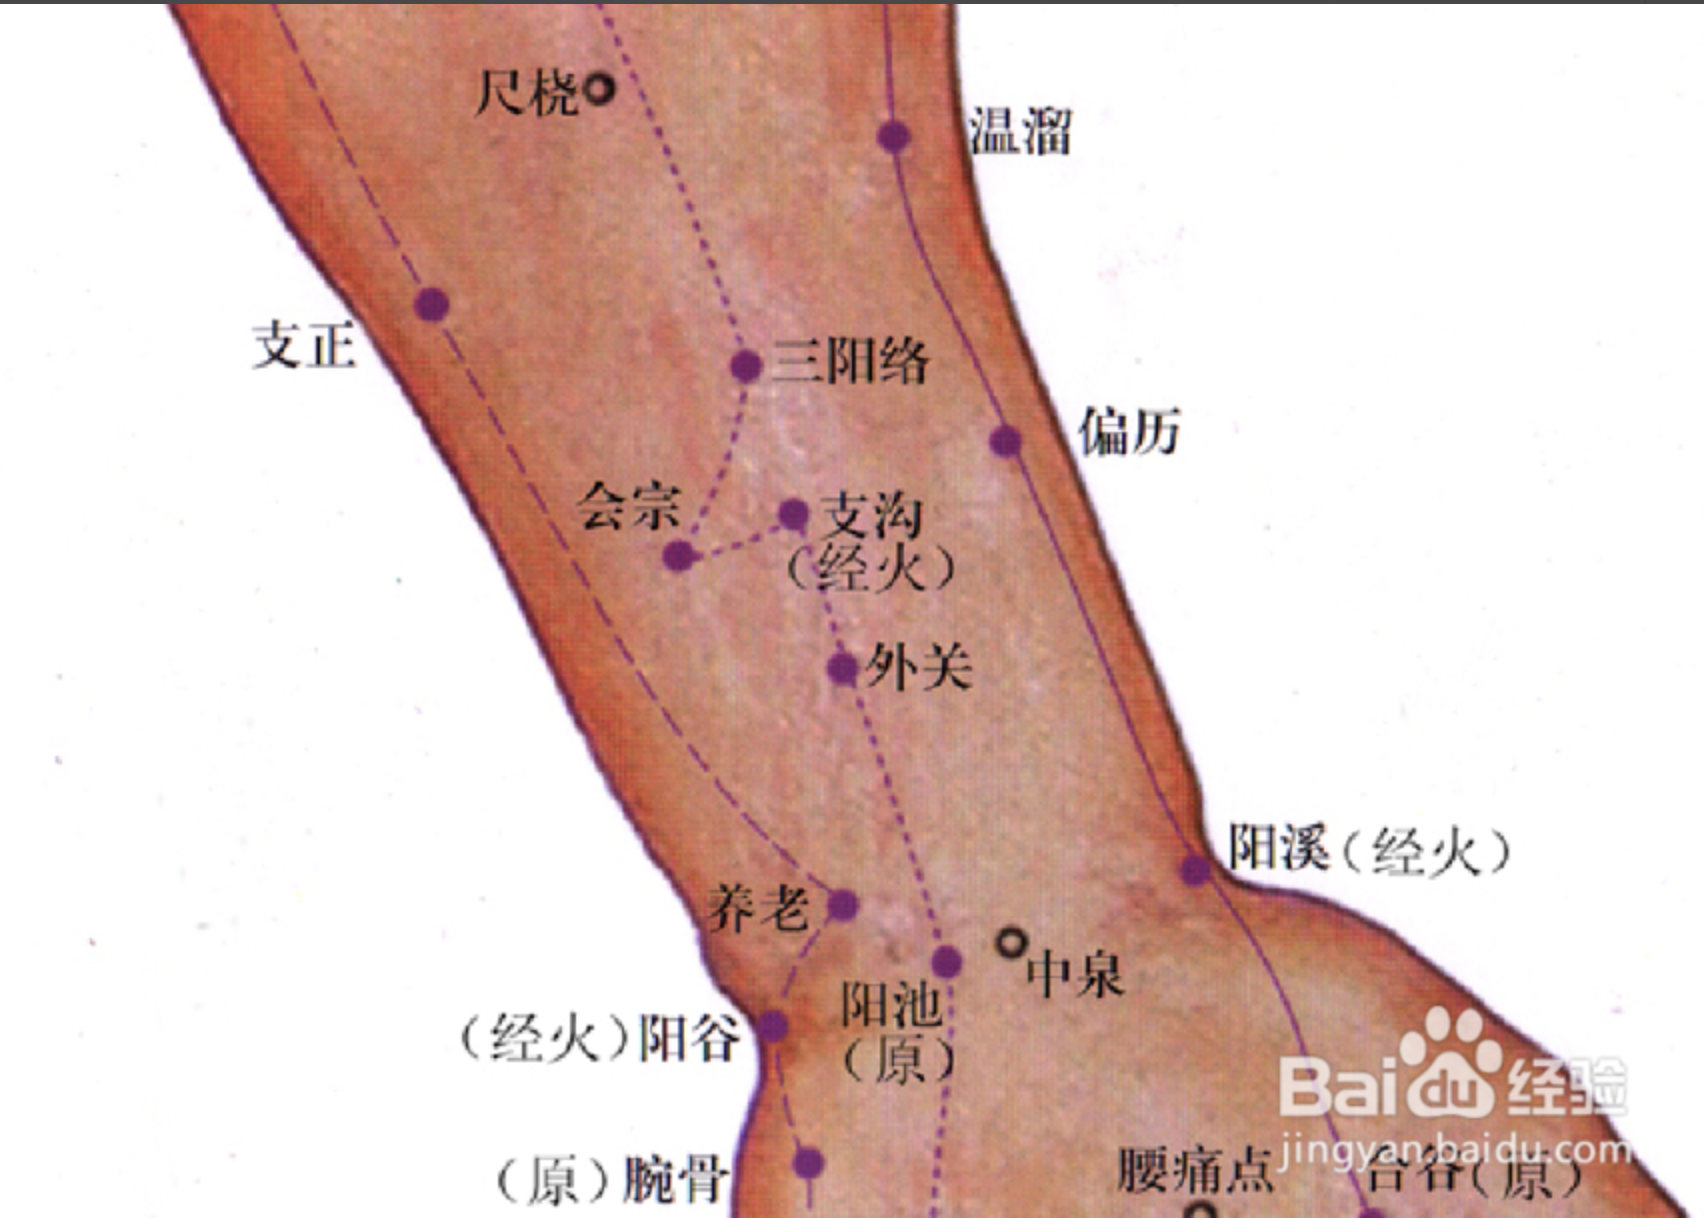

【(十)手少阳三焦经(图10-28)】

2、歌诀 二十三穴手少阳,关冲液门中渚旁。阳池外关支沟正,会宗三阳四渎长。天井清冷渊消泺(luò),臑会肩髎天髎堂。天牖(yǒu)翳风瘛(chì)脉青,颅息角孙丝竹空。和髎耳门听有常。

3、经脉循行 起于无名指末端(关冲)上行于第 4、5掌骨间,沿腕背、出于前臂外侧尺桡骨之间,经肘尖沿上臂外侧达肩部,交大椎,再向前入缺盆部,分布于胸中,络心包,过膈,从胸至腹,属于上、中、下三焦。

胸中支脉:从胸向上出于缺盆部,上走项部,沿耳后直上至额角,再下行经面颊部至目眶下。

耳部支脉:从耳后入耳中,出耳前,与前脉交叉于面颊部,到目外眦,与足少阳胆经相接。

4、主要病候 腹胀、水肿、遗尿、小便不利、耳聋、咽喉肿痛、目赤肿痛、颊肿、耳后、肩臂肘外侧痛等。

5、主治概要 主治侧头、耳、目、胸胁、咽喉病、热病及经脉循行部位的其他病证。

关冲

【定位】 在手无名指末节尺侧,距指甲角 0.1 寸(指寸)。

【主治】 头痛,目赤,耳聋,耳鸣,喉痹,舌强,热病,心烦。

【配伍】 配内关、人中治中暑、昏厥。

【刺灸法】 浅刺 0.1 寸,或用三棱针点刺出血;可灸。

【附注】 三焦经井穴。

中渚(zhǔ)

【定位】 在手背部,当无名指本节(掌指关节)的后方,第 4、5 掌骨间凹陷处。

【主治】 头痛,目眩,目赤,目痛,耳聋,耳鸣,喉痹,肩背肘臂酸痛,手指不能屈伸,脊膂(lǚ)痛,热病。

【配伍】 配角孙治耳鸣耳聋,配太白治大便难,配支沟、内庭治嗌(ài)痛。

【刺灸法】 直刺 0.3 ~ 0.5 寸;可灸。

【附注】 三焦经腧穴。

外关

【定位】 在前臂背侧,当阳池与肘尖的连线上,腕背横纹上 2 寸,尺骨与桡骨之间。

【主治】 热病,头痛,颊痛,耳聋,耳鸣,目赤肿痛,胁痛,肩背痛,肘臂屈伸不利,手指疼痛,手颤。

【配伍】 配足临泣治颈项强痛、肩背痛,配大椎、曲池治外感热病,配阳陵泉治胁痛。

【刺灸法】 直刺 0.5 ~ 1 寸;可灸。

【附注】 三焦经络穴,八脉交会穴之一,通阳维脉。

支沟

【定位】 在前臂背侧,当阳池与肘尖的连线上,腕背横纹上 3 寸,尺骨与桡骨之间。

【主治】 暴喑(yīn),耳聋,耳鸣,肩背酸痛,胁肋痛,呕吐,便秘,热病。

【配伍】 配天枢治大便秘结,配双侧支沟治急性腰扭伤、胁痛。

【刺灸法】 直刺 0.5 ~ 1 寸;可灸。

【附注】 三焦经络穴。